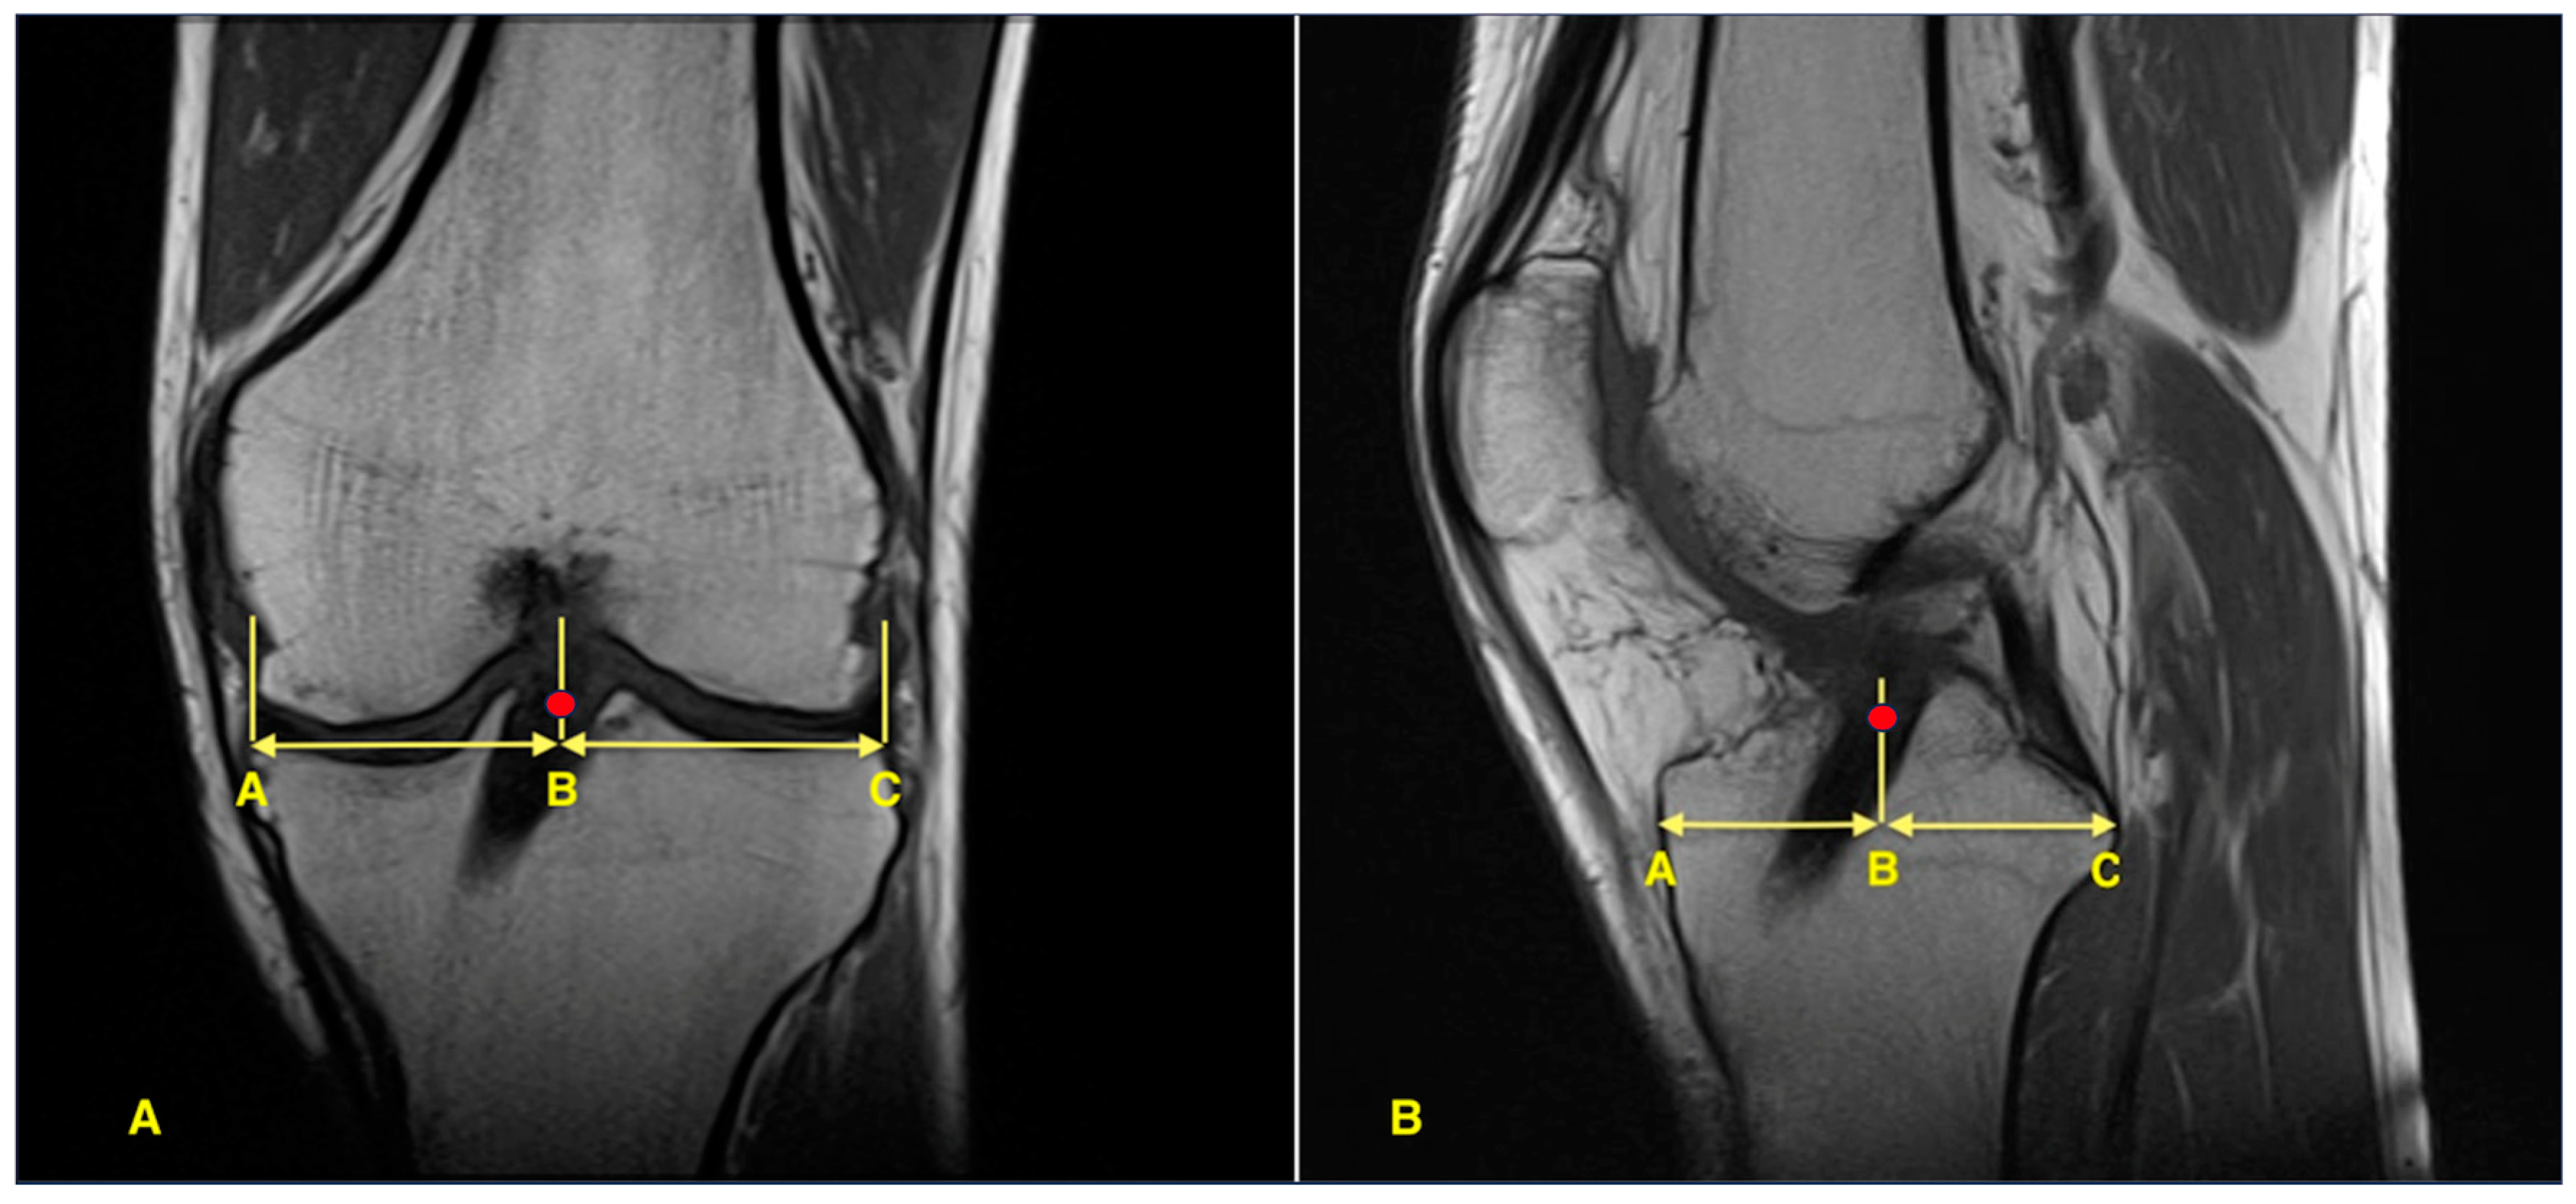

Post-operative MRI scans were obtained at 12 months after surgery. All MRIs were performed using a 1.5-T scanner (MAGNETOM Symphony; Siemens AG, Erlangen, Germany) with 3-mm slice thickness, including standard knee protocols (sagittal and coronal proton density–weighted sequences with fat suppression). Tibial tunnel positions were evaluated on sagittal and coronal images. Sagittal tunnel location was measured as a percentage of the anteroposterior tibial plateau length based on the method described by Stäubli and Rauschning [15], while coronal tunnel position was calculated as a percentage of the mediolateral tibial plateau width as described by Agneskirchner et al. [16] (see Figure 1).

Figure 1. Measurement of tibial tunnel position on post-operative MRI. The red dot indicates the center of the graft. (A) Coronal view showing mediolateral tunnel position calculated as the percentage ratio AB/AC. (B) Sagittal view showing anteroposterior tunnel location calculated as the percentage ratio AB/AC.